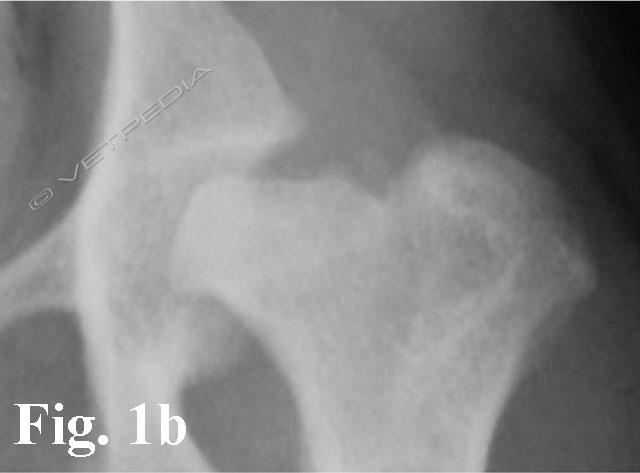

{{/_source.additionalInfo}}La necrosi asettica della testa del femore è anche denominata malattia di Legg Calvè Perthes e necrosi avascolare della testa del femore. Si tratta di un'affezione ortopedica coinvolgente l’articolazione coxofemorale di cani di razza toy o di piccola taglia durante il periodo dell’accrescimento, ad interessamento più frequentemente monola